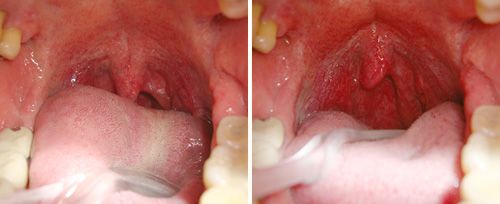

Clinical Results